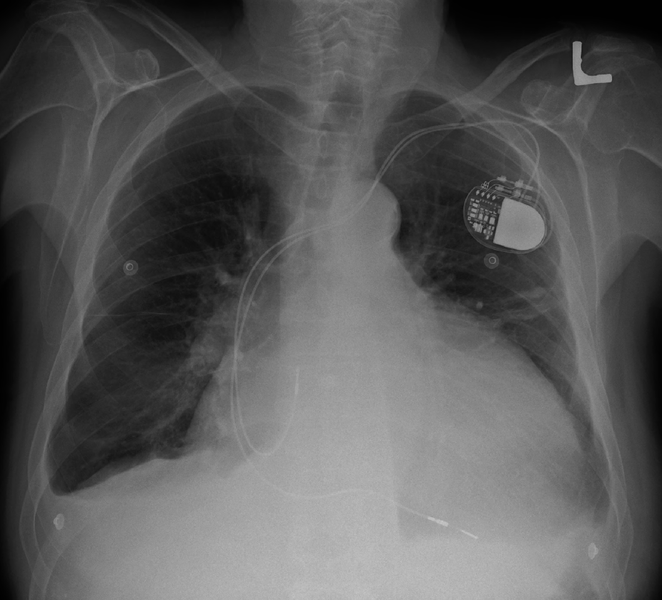

Here is a chest x-ray from someone with an enlarged heart. You an also see a pacemaker in the image:

Chest X-Ray with ICD. In this image, you can see an ICD, or “implantable cardioverter defibrillator.” An ICD is an extremely useful medical device that can prevent sudden death in patients who have problems with their heart rhythm. The device is implanted inside the body and tracks the heart rate. Wires (labeled “pacing lead” and “shock lead”) connect the ICD generator to the heart. If the device detects a dangerous heart rhythm, it will shock the heart to restore a normal heartbeat. If you have ever watched a medical TV drama, an ICD is like a miniaturized, implanted version of those paddles that they put on the chest and yell “CLEAR” to wake someone up.